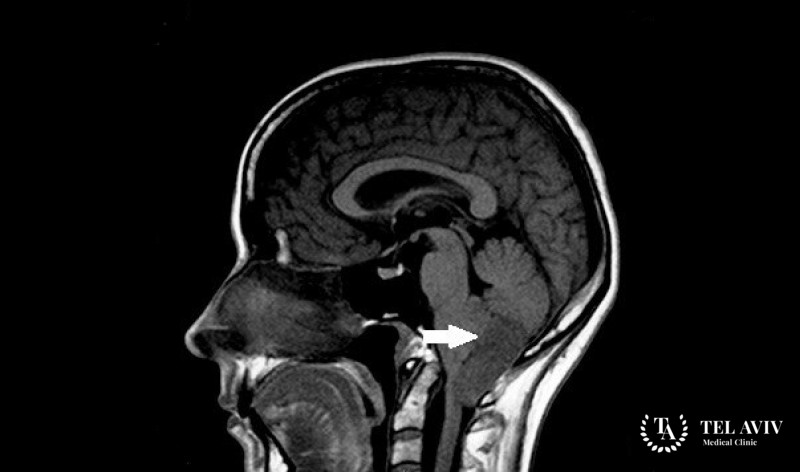

Субэпендимома – является злокачественной опухолью головного мозга, которая состоит из субэпендимальной глии и клеток. Образование имеет форму узла и зачастую расположено в желудочковой системе мозга. Врач, который обнаружил данное заболевание приступает к немедленному лечению. Пациенты с таким недугом довольно быстро выздоравливают. Терапия является эффективном при данном недуге. Человек может даже не знать о развитии опасной патологии, так как симптомы выражены крайне слабо. С течением времени опухоль значительно увеличивается в размерах и начинает сдавливать ближайшие ткани.

В качестве диагностики врач использует лабораторные методы исследования и визуализацию проблемного участка. Затем на основе полученных данных подбирает схему терапии с учетом типа и характера патологии, а также общего состояния больного.